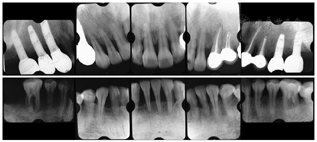

(6)复查及维护:戴牙完成后每半年规律复查及牙周维护治疗。

末次复查结果显示患者口腔卫生状况良好,牙周状况稳定(图11,图12,图13)。解决了前牙间隙问题,恢复了后牙的咀嚼功能,患者对疗效满意。